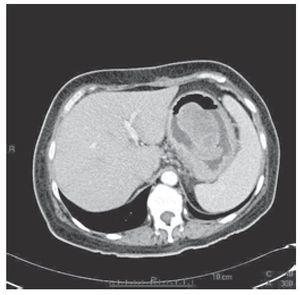

Se tomaron múltiples biopsias que demostraron gastritis crónica y aguda intensa ulcerada. Debido a esto la paciente se llevó a cirugía donde se encontró un gran tumor gástrico en el fondo que requirió gastrectomía total con esófago yeyuno anastomosis en Y de Roux. El reporte final de patología fue pólipo fibroide inflamatorio de 9.1x6.3 cm fascina (+), ciclina D1 (+), c-kit (-), CD34 (-) (Figuras 2-4). La evolución posoperatoria fue satisfactoria, siendo egresada la paciente después de 10 días de estancia hospitalaria.

Figura 3. Proliferación de células fusiformes de aspecto fibroblástico sin atipia que alternan con linfocitos, células plasmáticas y algunos eosinófilos. Se observa acentuado edema del estroma (40X).

Los pólipos fibroides inflamatorios son un tipo raro de tumor mesenquimatoso no neoplásico del tracto gastrointestinal. Ocurren principalmente en el estómago como pólipos localizados, y menos frecuente en el intestino delgado, colon y esófago en orden decreciente.4 Esta entidad fue descrita por primera vez en 1949 por Vanek como "un granuloma gástrico submucoso con infiltración eosinofílica".5 Microscópicamente está constituido por células estromales fusiformes con abundantes vasos sanguíneos pequeños con un infiltrado inflamatorio dominado por eosinófilos. Debido a la naturaleza polipoide y la disposición característica de elementos fibrosos y vasculares, Helwig y Ranier fueron los primeros en usar el término de PFIG.6 El origen celular no está totalmente esclarecido, aunque la hipótesis más aceptada es que se origina de células dendríticas debido a su perfil inmunohistoquímico, donde siempre son positivos para CD34, fascina y ciclina-D1, así como la ausencia de c-kit confirma su no asociación con los tumores del estroma gastrointestinal (GIST).7